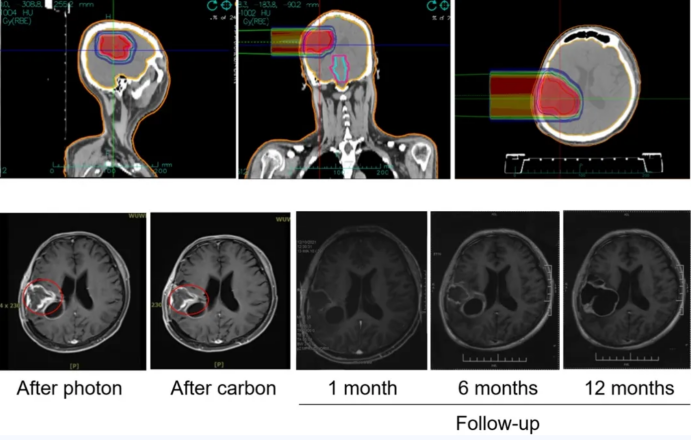

作为国内率先开展重离子治疗肿瘤的临床科室,本科室的工作重点聚焦于运用重离子治疗鼻咽癌、颅底肿瘤、脊索瘤以及脑胶质瘤等疑难病症。这一实践为国内重离子治疗标准的构建提供了具有重要价值的循证医学依据。同时,科室开展了“光子联合重离子治疗高级别脑胶质瘤的二期临床研究”。此项目意味着科室在攻克最难治的脑肿瘤这一领域取得了关键进展。本研究的目的在于为高级别脑胶质瘤患者提供一个有望显著延长生存期、改善生活质量的新契机和更优的治疗方案。初步研究数据已呈现出令人振奋的治疗效果以及良好的安全性。